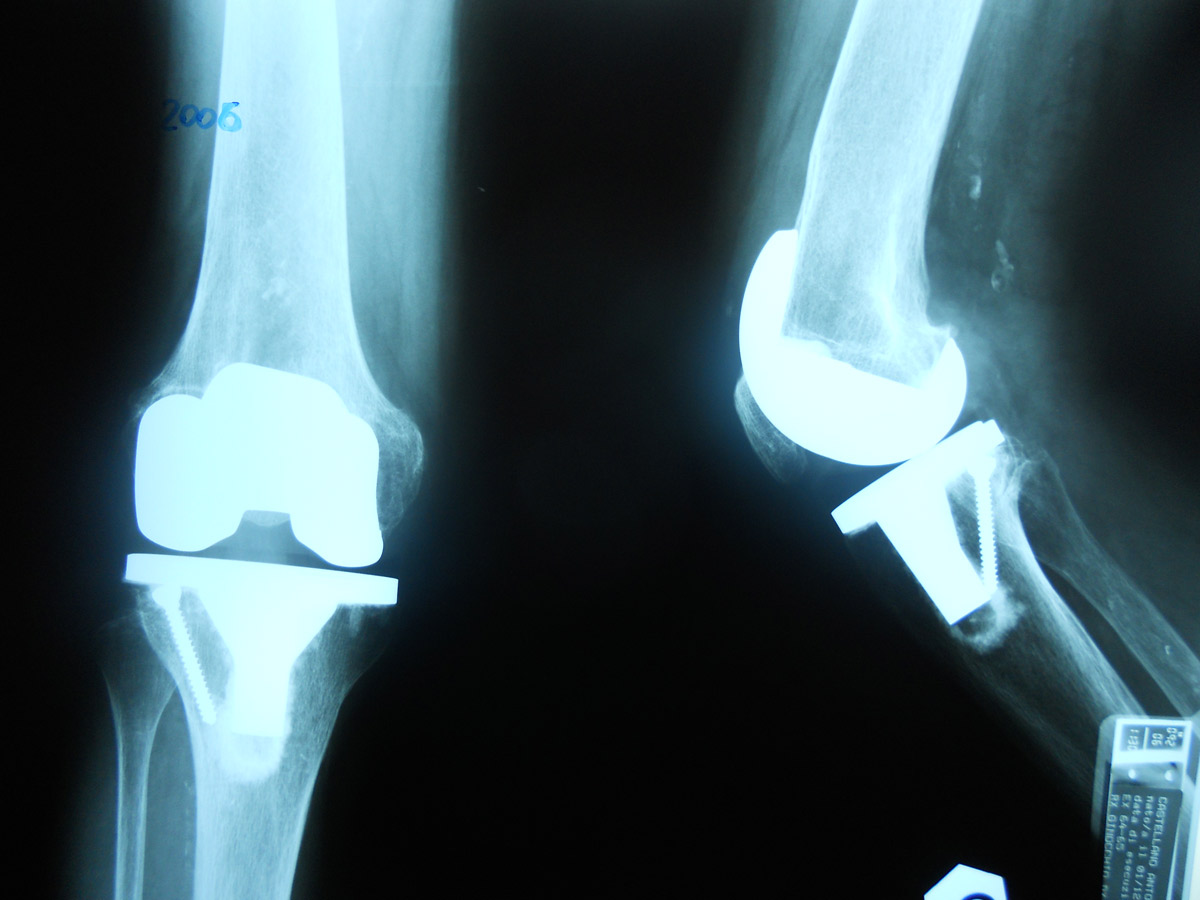

protesi ginocchio grave deformità

Caso clinico di paziente di 85 anni con artrite reumatoide e lussazione congenita d’anca controlaterale (deambulazione con rialzo di 6 cm), ormai costretta su una carrozzina a causa della grave deformità e instabilità del ginocchio destro. Questo caso dimostra che non esiste deformità che non possa essere corretta con un buon intervento di impianto protesico di ginocchio.

Fig. 2 Radiografia postoperatoria a 2 anni dall’intervento che dimostra la perfetta integrazione dell’innesto osseo (vite) e l’asse del ginocchio ripristinato alla normalità